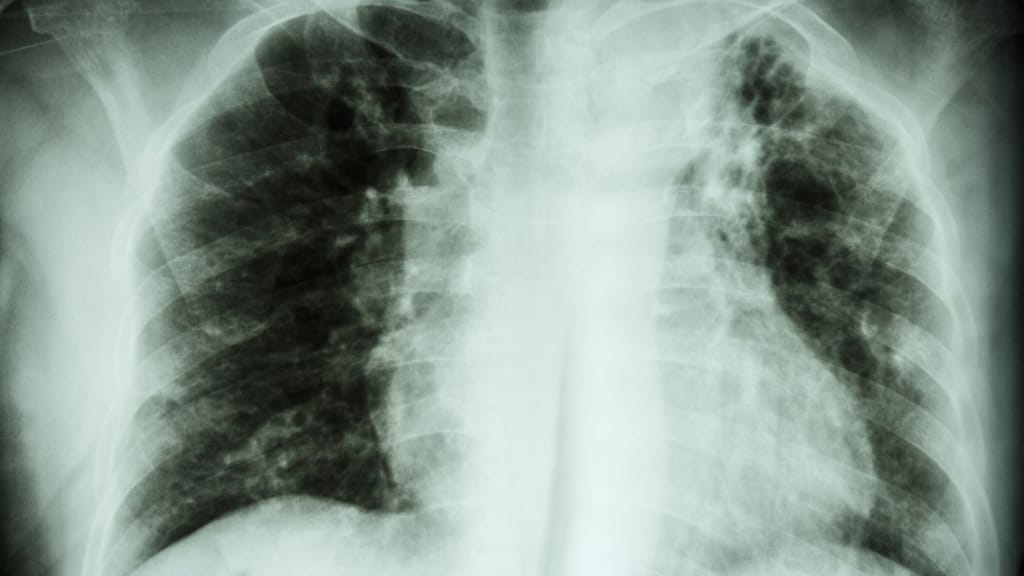

La tuberculosis es una enfermedad infecciosa causada por la bacteria Mycobacterium tuberculosis, que afecta principalmente los pulmones. Pero también puede dañar otros órganos del cuerpo, como los riñones, el cerebro y los huesos.

"En cada consultorio hay un equipo de tuberculosis que le hace una muestra, una radiografía de tórax y un control médico. Con eso se determina si tiene o no esta enfermedad", señala la enfermera.